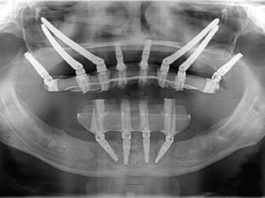

Protesi Totale e Toronto, quali connessioni?

Un collega mi ha confessato di non conoscere la protesi mobile, quindi progetta e costruisce dispositivi di Toronto in quanto protesi fissa.

Dice di...